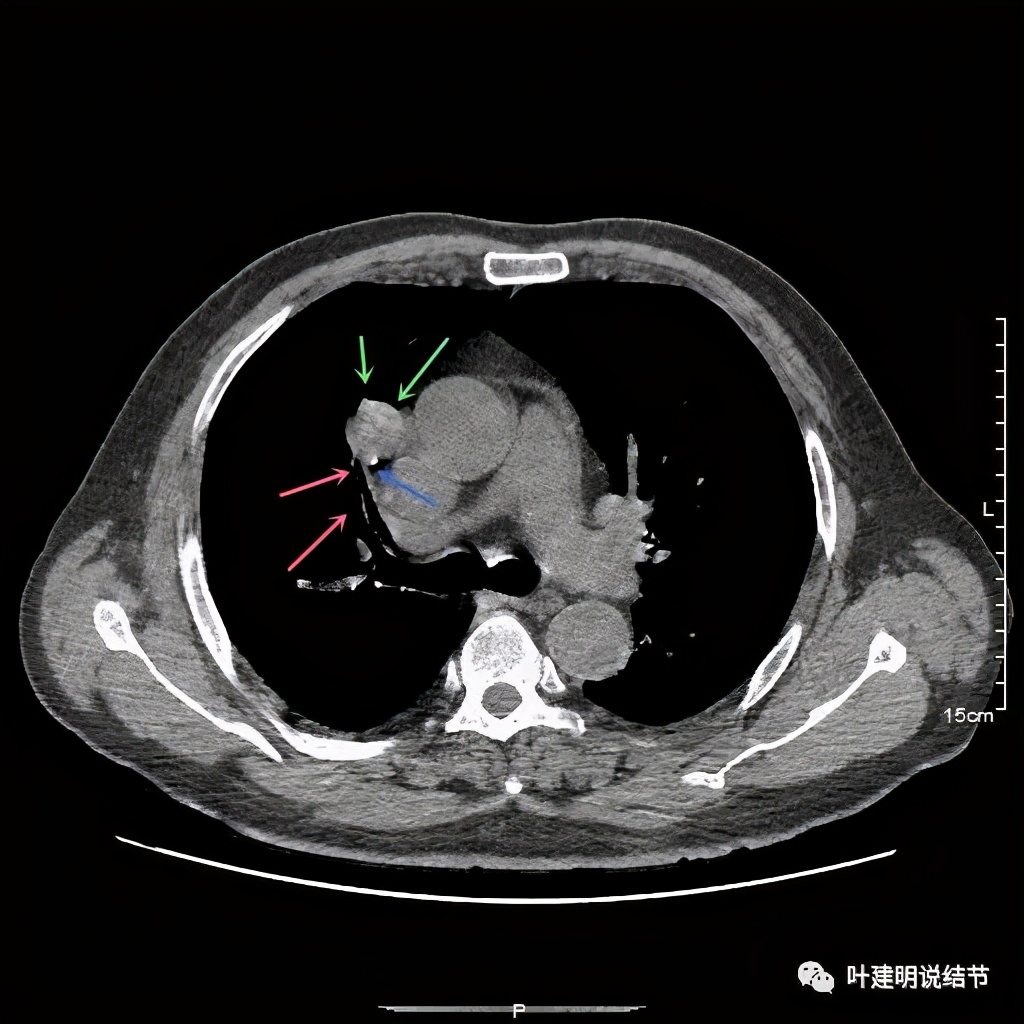

上图示病灶局部点状高密度(蓝色);边缘过于光滑(绿色)

上图示病灶密度不均,但边缘过于光滑(绿色);支气管似有截断(粉色);局部有点状钙化(蓝色)

上图也示病灶密度不均,但边缘过于光滑(绿色);支气管似有截断(粉色);局部有点状钙化(蓝色)